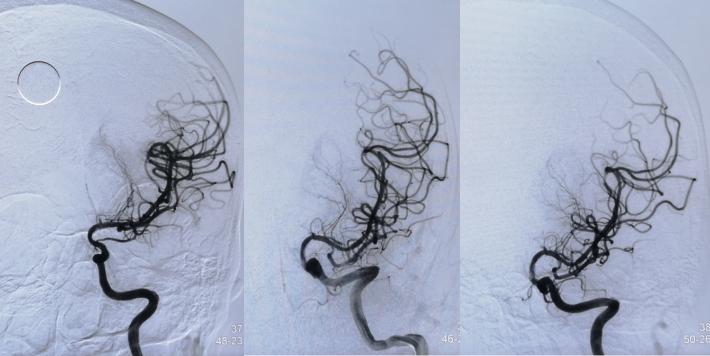

4.5mm*22mm Enterprise 支架

术 后

✔支架选择:左侧颈内动脉虹吸段狭窄段长度较长,远端至左侧大脑中动脉M1起始段,近端至眼动脉开口上方。且此段血管迂曲,狭窄段近端、远端都有较大的血管转折,使用球扩支架风险很高。因此我们选用了顺应性较好,又有一定支撑力的自膨支架——Enterprise 支架。

✔术中要点:左侧颈内动脉虹吸段狭窄考虑为夹层,予反复多个角度导引导管造影,以明确真假血管腔,微导丝通过狭窄段血管时谨慎、轻柔操作,务必判断导丝应从真腔通过。先予球囊扩张,观察扩张后狭窄段血管管径恢复情况。释放前准确定位支架近端,远端,应完全覆盖狭窄血管段。